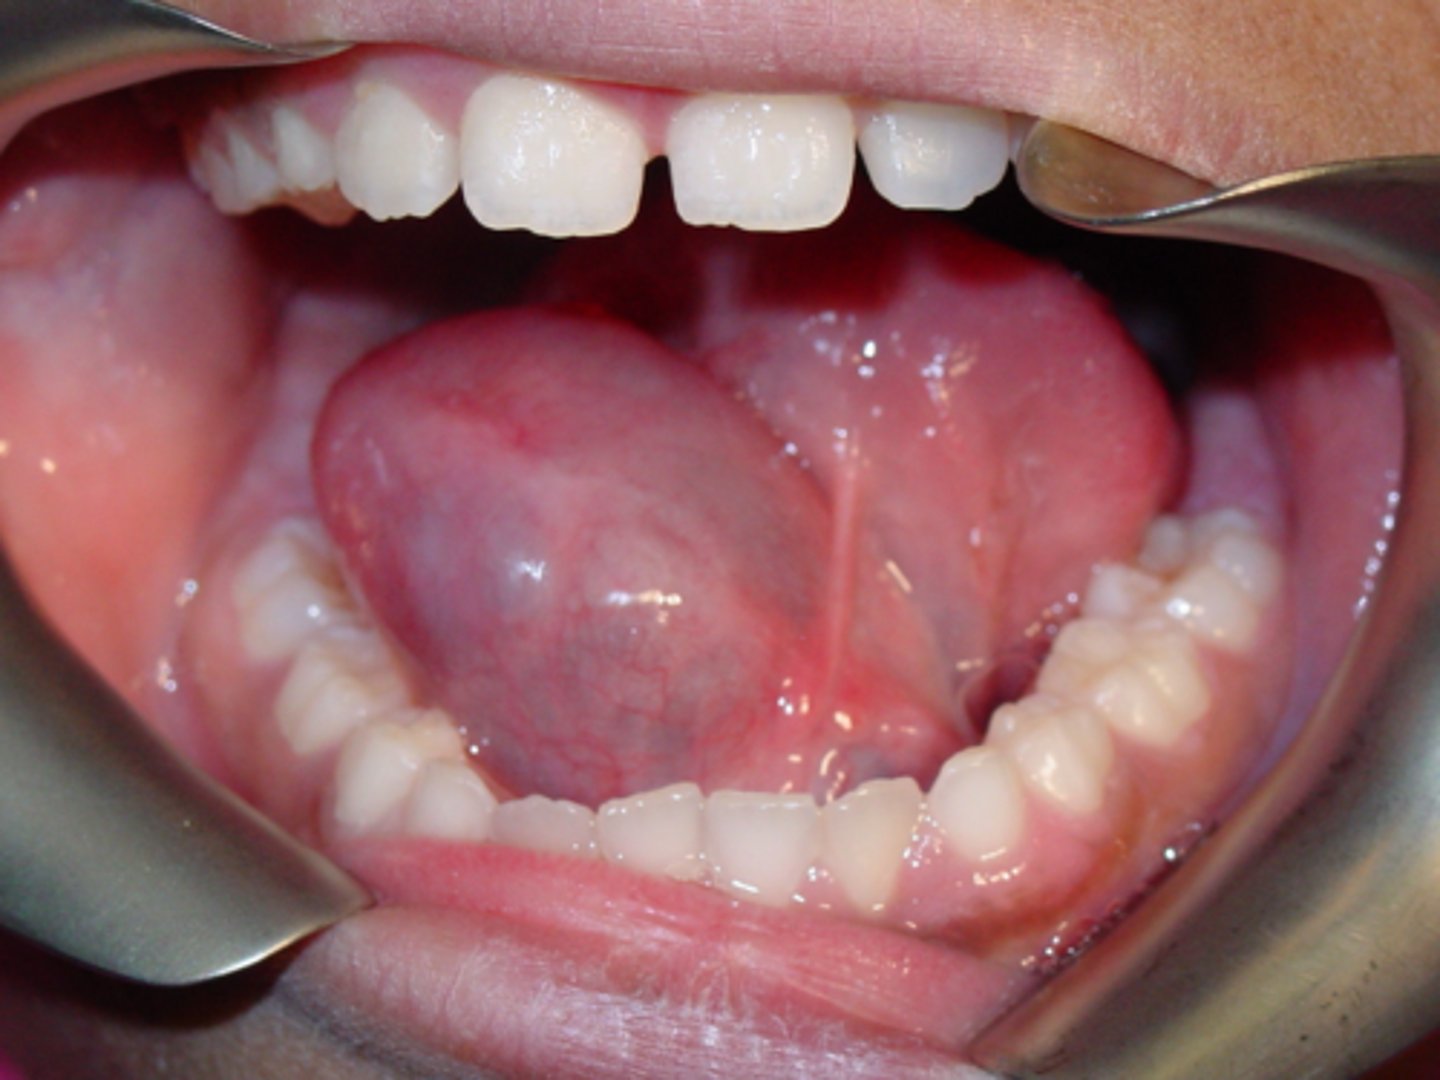

ID the pathology:

- Common reactive salivary gland lesion

- - Traumatized duct spills mucus into adjacent tissues

- Characteristic hx of increasing/decreasing in size

Mucocele

- Dome-shaped fluctuant vesicle

- Blue or mucosa-colored

- Most common on lower lip

- - May be seen anywhere w/ salivary glands

- Traumatized duct spills mucus into adjacent tissues

- Characteristic history of increasing and decreasing in size

lower lip

What is the most common location for mucocele to present?